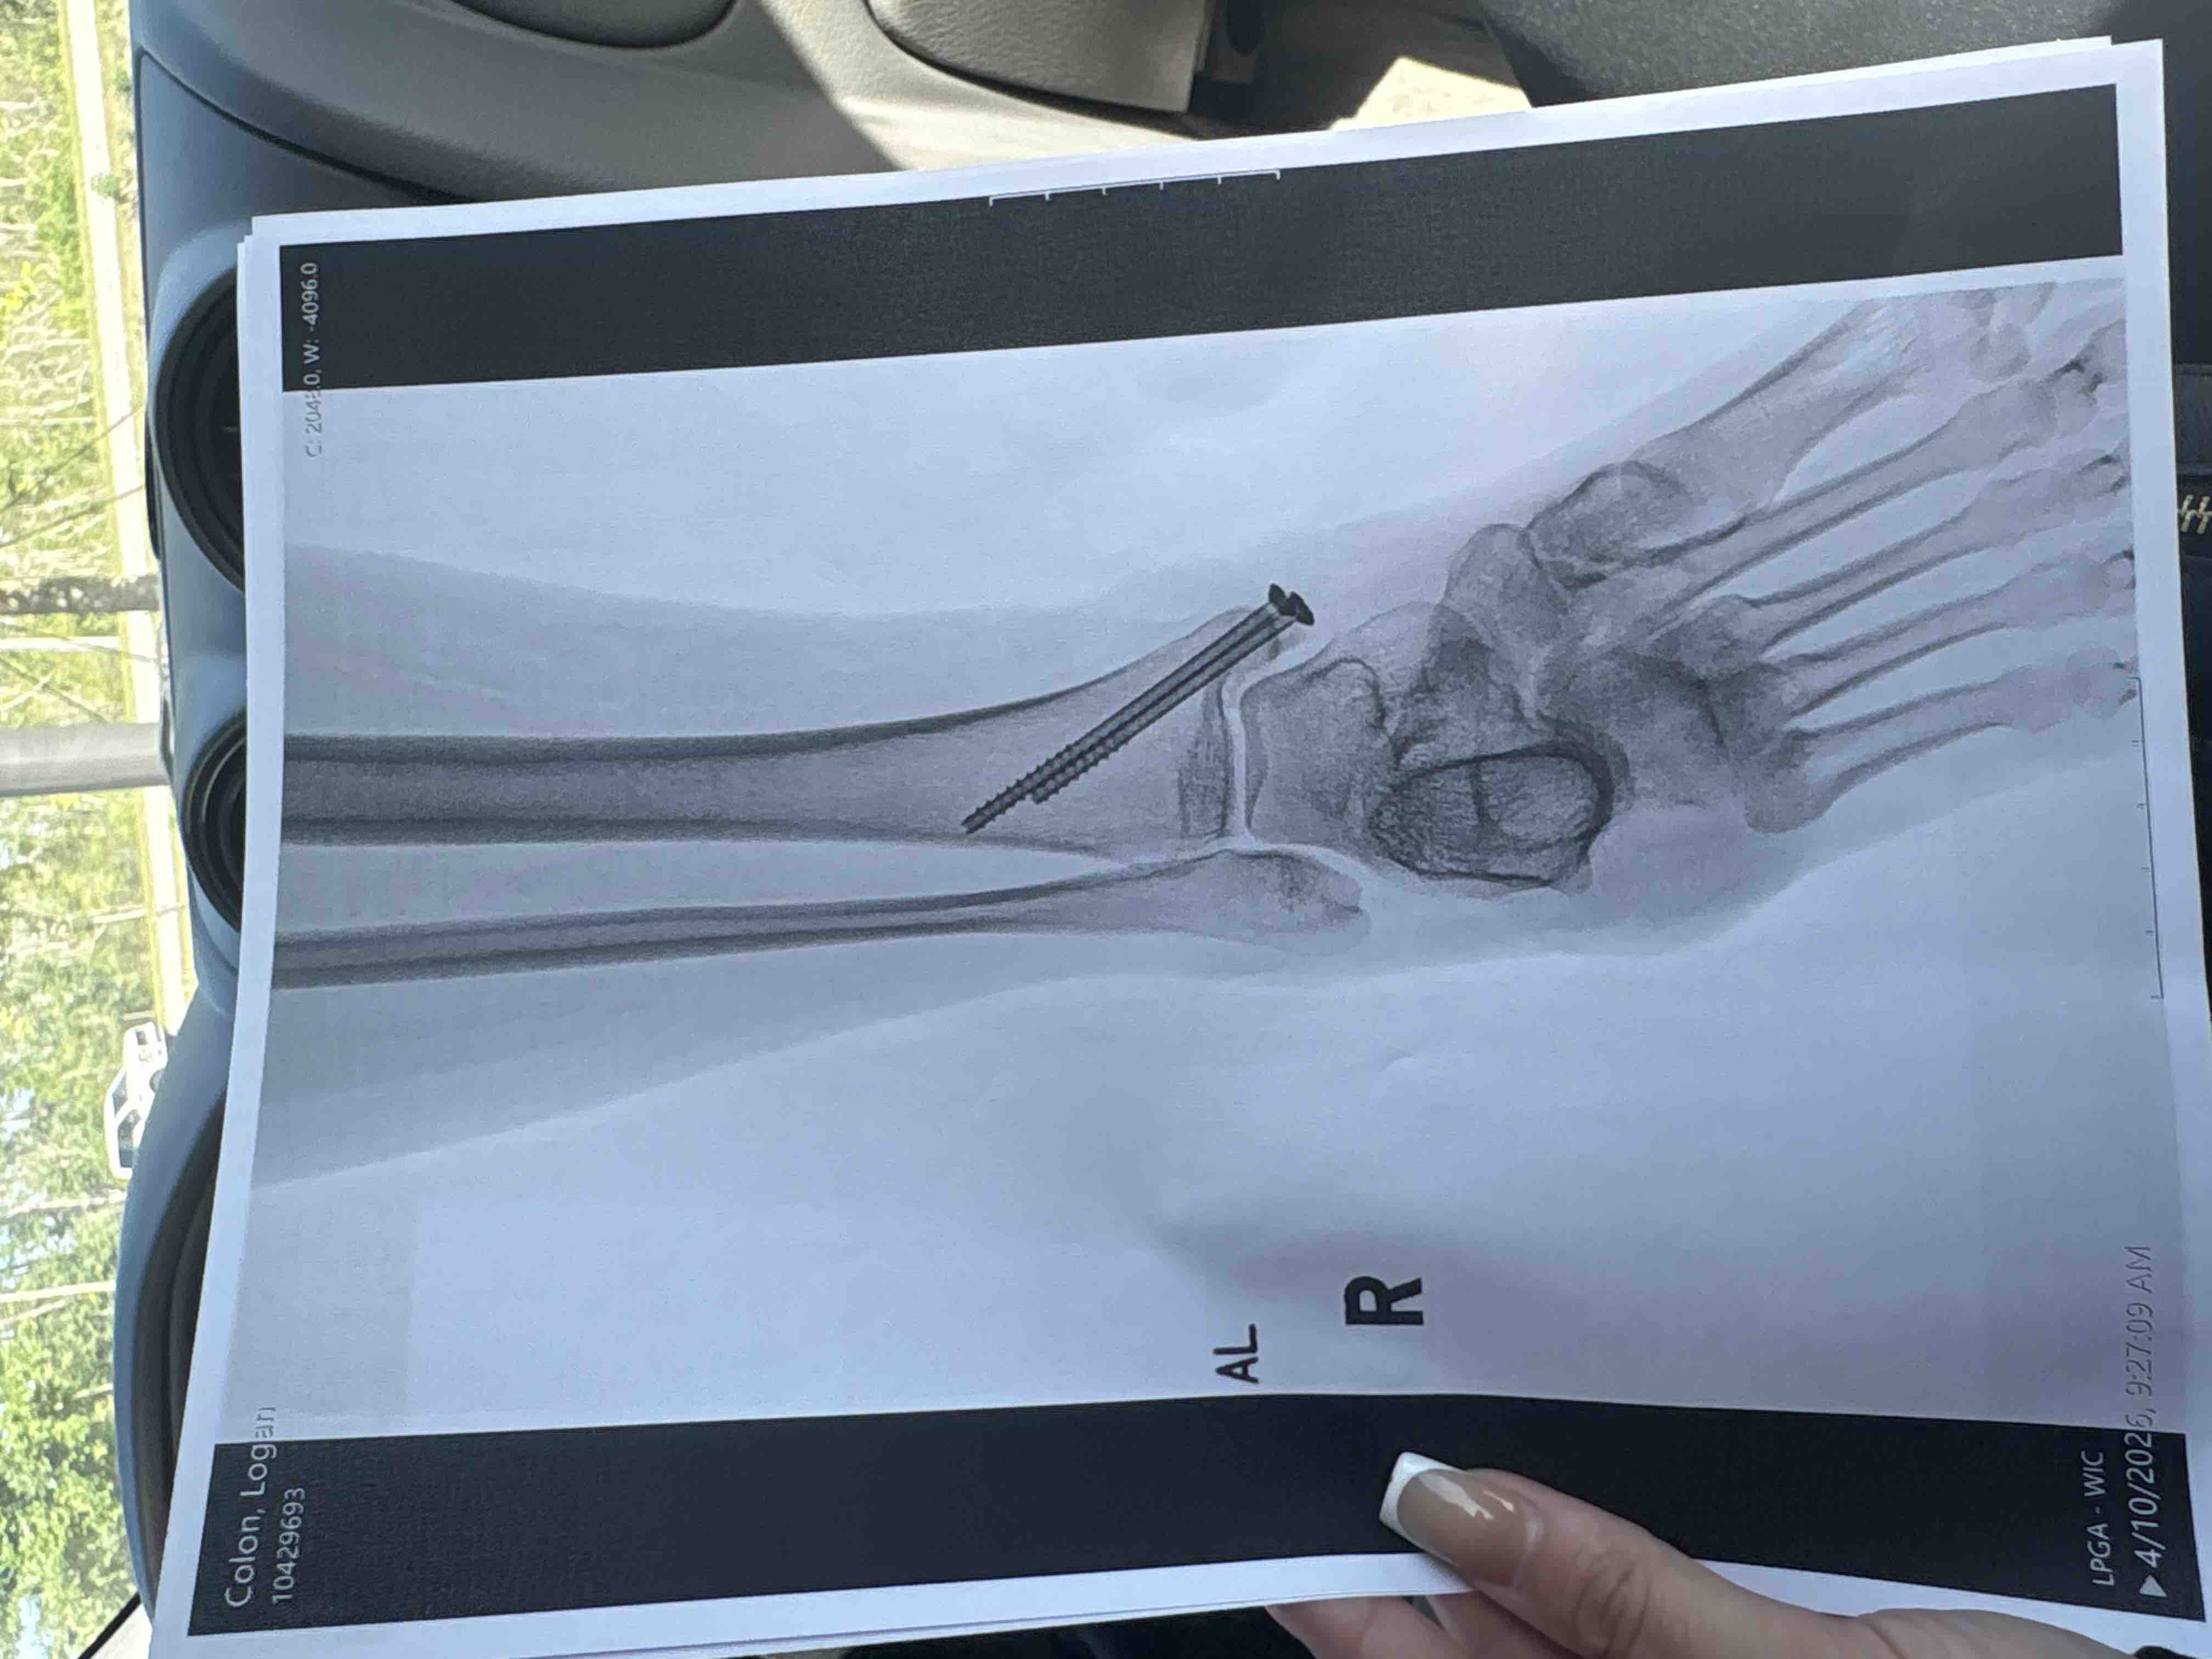

My car was immediately deemed totaled. I had just bought the car with cash only 3 months ago, but that isn’t what I am creating this for. The emts cut my pants because I had a deep to the bone laceration. I had then got into the ambulance and to Halifax I went. I could barely move my right leg especially ankle, was veryyy bruised / swollen. After some x rays what I had hoped was not the case in fact was. Three fractures in my right ankle as well as a fractured patella inside the laceration.. resulting in surgery + 2 screws in my ankle for life + 8 stitches on ankle, 12 stitches on knee and 2 inside knee.